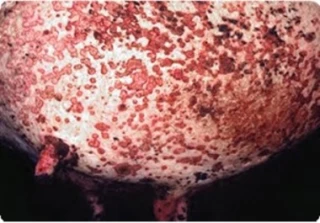

Lors d’une conférence de presse au Sommet de l’élevage le 7 octobre, le président de la FNPL (producteurs de lait, FNSEA) Yohann Barbe a exigé des « garanties » sur l’indemnisation des pertes de production de lait dues à la dermatose nodulaire contagieuse (DNC). Un sujet prégnant alors que le repeuplement se profile dans l’Ain et les deux Savoie, où la zone de protection vient d’être levée. « La prise en charge ne porte que sur trois mois. Or, reconstituer un troupeau laitier dans ce délai, c’est impossible », explique Yohann Barbe. « On a l’impression qu’on essaie de nous calquer sur les schémas d’élevage hors sol », analyse-t-il, réclamant une durée de prise en charge plus longue. D’après cet éleveur vosgien, la ministre de l’Agriculture démissionnaire avait déjà « opposé une fin de non-recevoir » à cette demande. Outre la mortalit&eacut...